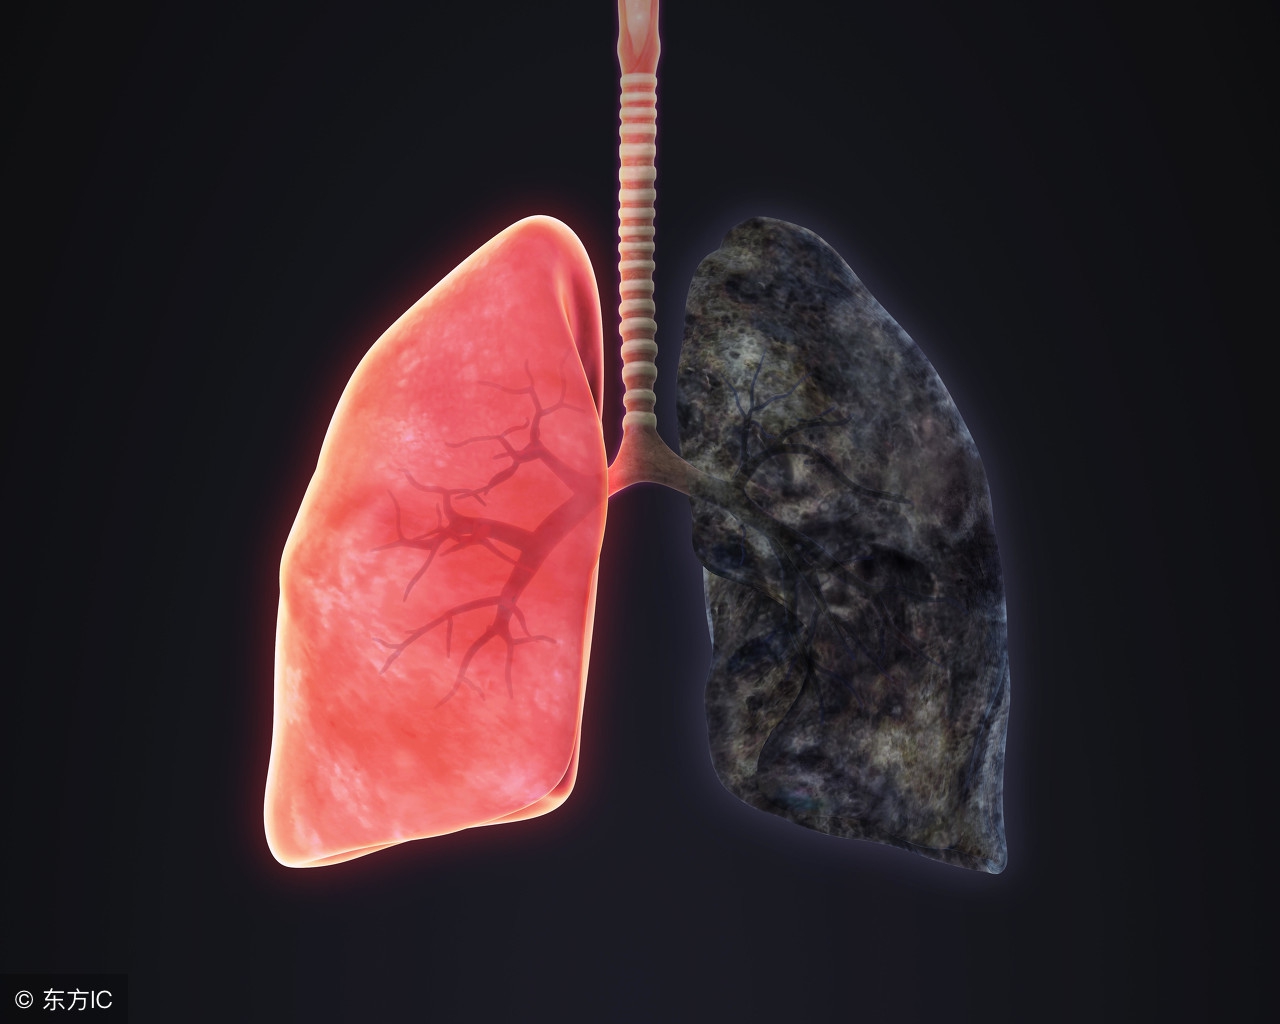

很多人在患上了支气管炎疾病之后不知道到底会不会出现发烧的现象,支气管炎是属于炎症感染很严重的一种疾病,如果是孩子患上了支气管炎这个疾病的话,那么要很长时间孩子的疾病才会治疗好,孩子的支气管炎会引起喘息的现象,喘息会让孩子难受,呼吸也比较困难,而孩子在支气管炎期间额头还会发烫,那么这个支气管炎会引起发烧吗?

支气管炎会引起发烧的,建议还是CT或者胸片检查和化验血常规看看.如果确诊支气管炎或者呼吸道感染引起的,可以遵医嘱服用消炎药和止咳祛痰药物对症治疗,如服用头孢克罗胶囊和复方甘草口服溶液等,一般不能盲目服用药物,使用抗生素需要医生指导下服用.发热超过38.5时再服用退热药.避免引起药物副作用或者细菌耐药性.注意休息和多喝白开水.避免辛辣刺激性饮食。